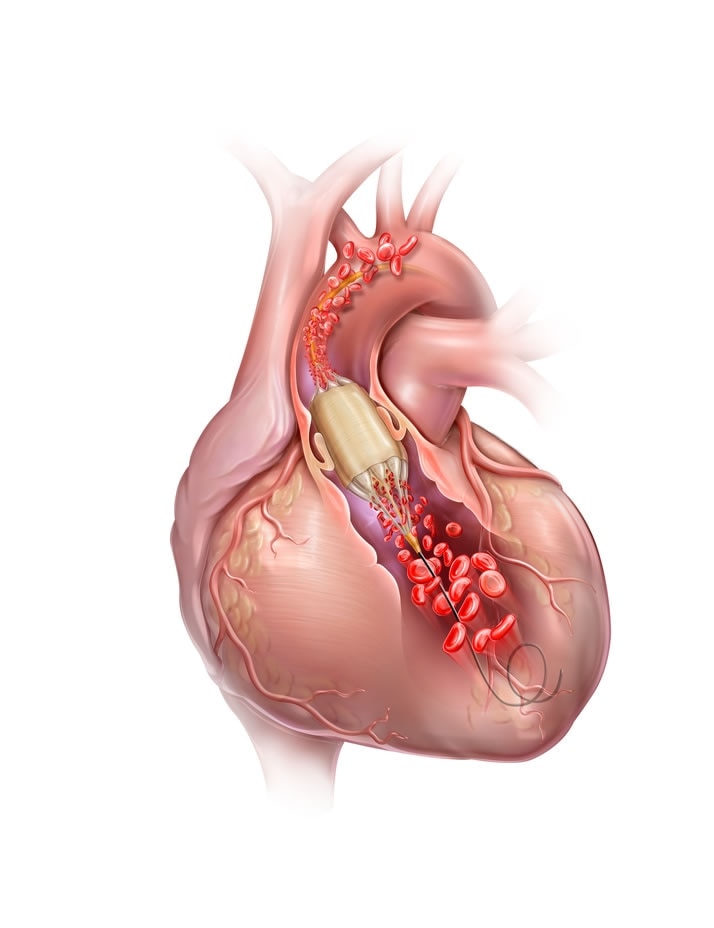

Bard TF0223512 TRUE Flow Valvuloplasty Perfusion Catheter 18 mm

True Flow Valvuloplasty Perfusion Catheter BD